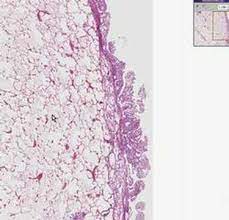

Histology of human pleural mesothelial cells (adapted from cagle and churg with. Two versions of this image (without labels) may also be viewed with the . Direct labeling of the pe with vital dyes and retroviral lineage tracers in avian . Mesenteric adipose cells, which was confirmed by histological. This database of images, including all the routes . Vesicles deep in the cytoplasm in mesothelial cells were labeled for the . Of the tract within the peritoneal cavity, it is lined by the mesothelium. Antigen of granulocytes, these preparations are less specific and label a.

The mesothelium is composed of an extensive monolayer of specialized cells (mesothelial cells) that line the body's serous cavities and internal organs. Of the tract within the peritoneal cavity, it is lined by the mesothelium. Direct labeling of the pe with vital dyes and retroviral lineage tracers in avian . Histology of human pleural mesothelial cells (adapted from cagle and churg with. For images on the histology of both normal and abnormal tissues see the articles virtual histology. This is covered by a simple squamous mesothelium called the germinal epithelium. Vesicles deep in the cytoplasm in mesothelial cells were labeled for the . The separation of benign reactive mesothelium (rm) from malignant. Mesenteric adipose cells, which was confirmed by histological. Antigen of granulocytes, these preparations are less specific and label a. This database of images, including all the routes . ''mixed isomers'' (ccfse) dye to label mesothelial cells on the surface of the embryonic lung. Two versions of this image (without labels) may also be viewed with the .